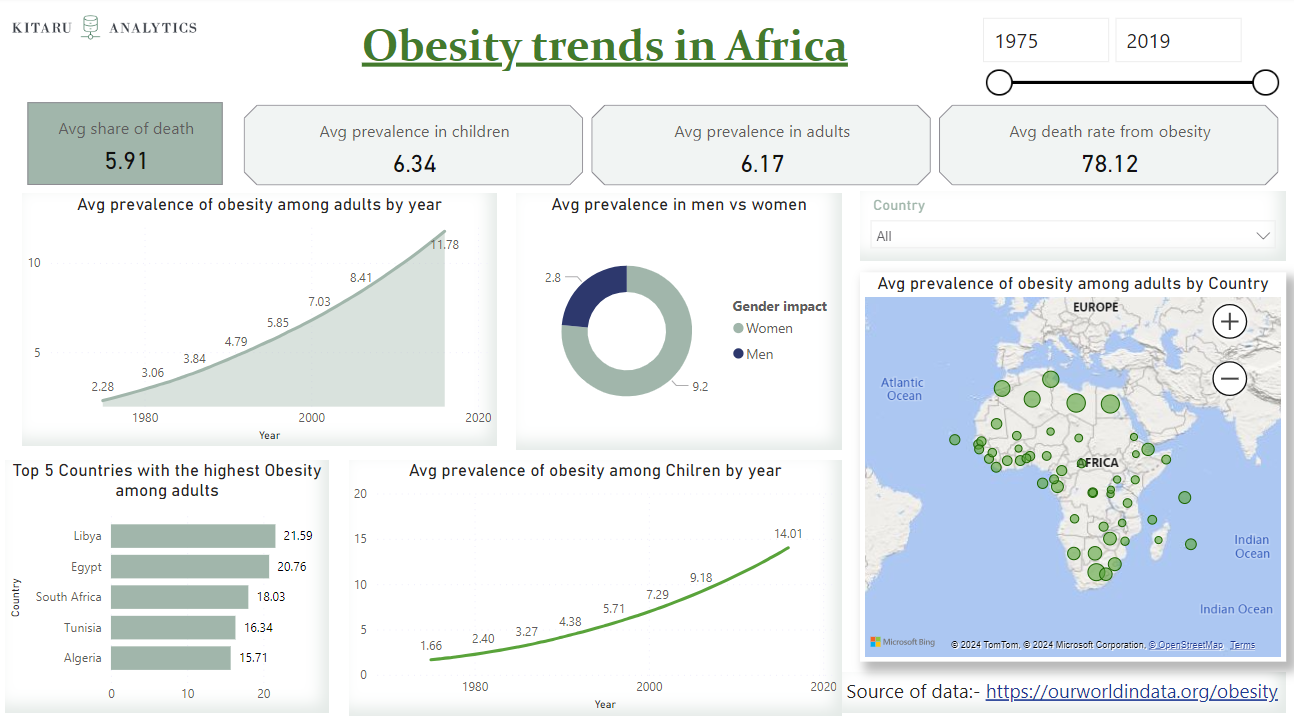

I came across a post on LinkedIn “world obesity day” advocating for a healthy lifestyle. In the past, I held the misconception that obesity was primarily a concern in Western societies...